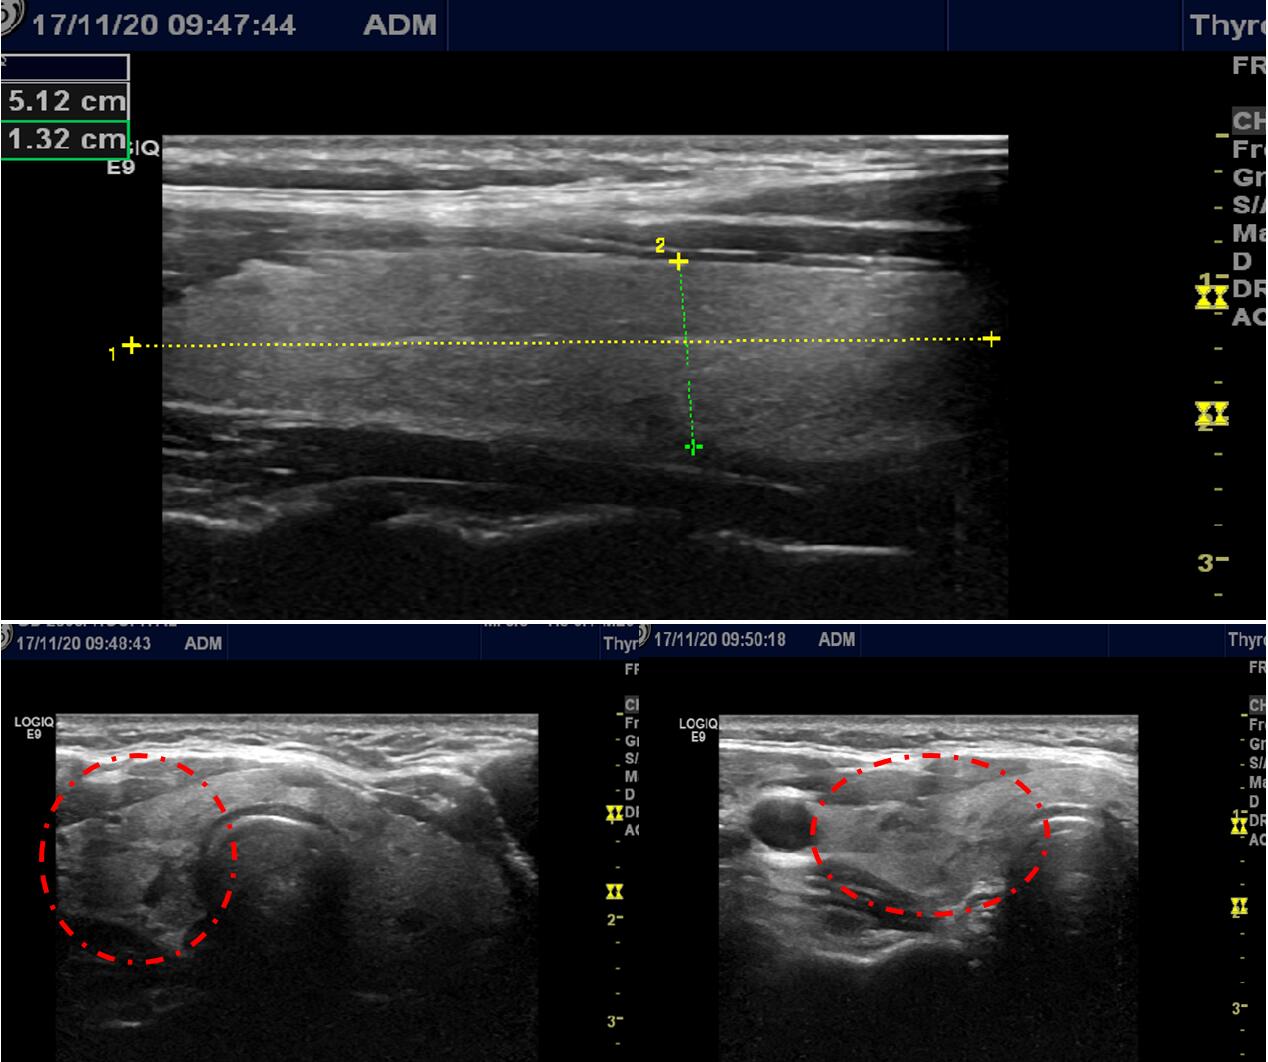

34岁的李女士2015年7月单位体检发现甲状腺双侧叶长了多个结节,最大的结节为23mm*15mm*13mm。李女士知道自己甲状腺长了多个结节则到当地医院就诊,医生认为李女士结节多个且较大结节超过两公分,需要治疗,因双侧也都有结节,手术切除范围大,术后很可能需要长期服用优甲乐,若不愿意开刀手术切除,则可以到广州行介入微创消融治疗,可以消灭结节的同时尽可能多的保留正常甲状腺组织。李女士观察且犹豫了半年,再次复查时甲状腺结节少许增大,部分囊性变,同时,李女士了解到广东省第二人民医院介入科是广东省较早开展甲状腺结节细针穿刺活检及甲状腺良性结节微创消融治疗的科室。李女士才下定决心到广州治疗,在广东省第二人民医院介入科就诊超声检查显示甲状腺双侧叶多发结节并结节部分囊性变(如下图)。#健康科普挑战赛#